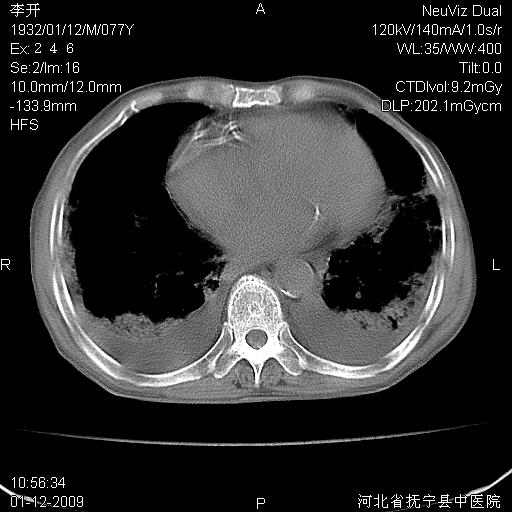

以下是引用黑白光影在2009-1-19 16:49:00的发言:[br]心衰肺水肿;心包、胸腔积液;冠脉钙化;肺部感染。